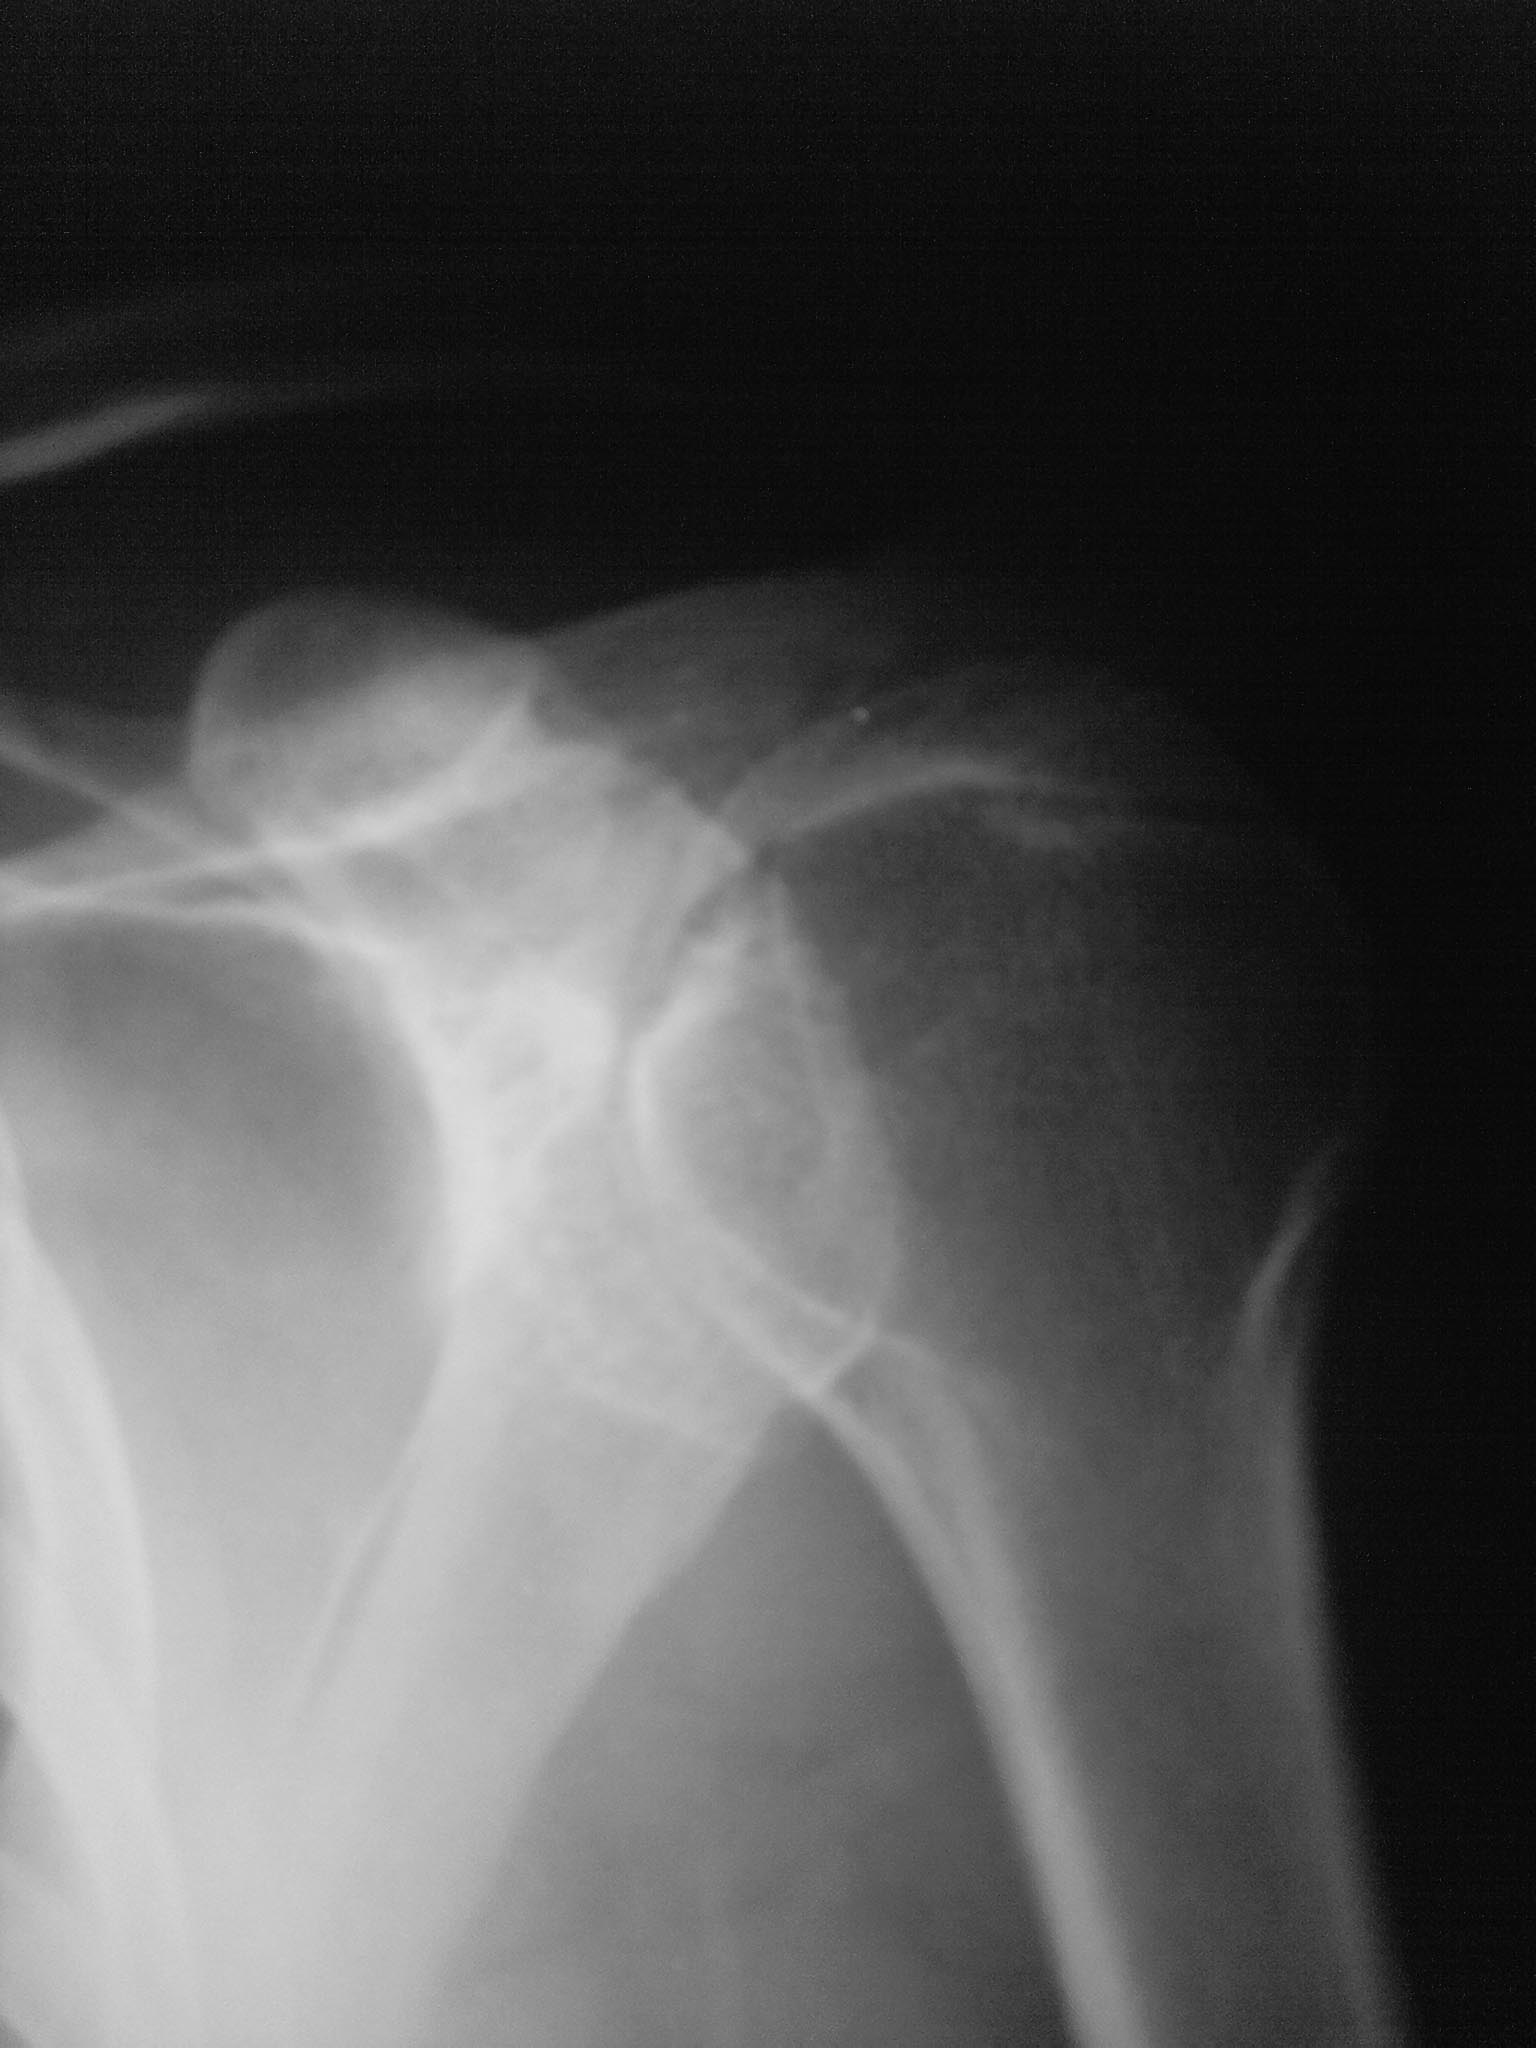

На рентгенографии рентгенологи описали артроз плече-лопаточного сустава.

У пациента была около 5 лет назад травма плечевого сустава-поскольку он

не обращался за помощью,то расскажу как он её описывает. Упал на плечо с

высоты собственного тела,чувствовал боль. С его слов ему дёрнули руку и

он почувствовал облегчение. Потом в течении около 2 лет было несколько

таких состояний,которые проходили когда ему знакомые "дёргали" руку.

Сейчас его беспокоят боли которые локализуются по задней поверхности

плечевого сустава,немного дистальнее акромиона. Боли чаще возникают

ночью,утром после работы руками-проходят. Иногда как он говорит,боли

возникают при положении руки кзади от спины.

При осмотре атрофии мышц нет. Тест отведения руки,тест jobe,симптом

импиджмента Neer отрицательный. При тесте болезненной дуги так же не

выявлено патологии.

Пробовал иньекционный тест Neer-он отметил уменьшение боли(но полностью

не прошли)